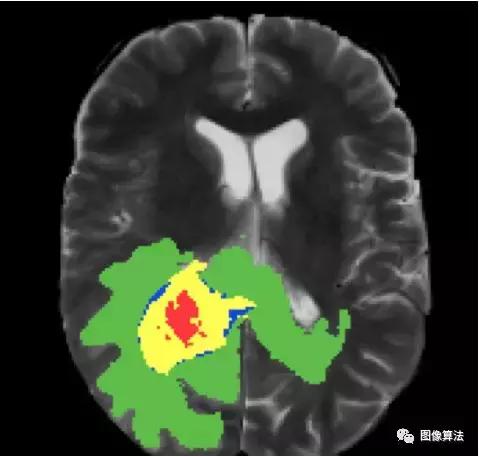

医学图像

身体扫描的自动分割可以帮助医生进行诊断测试。例如,可以训练模型以分割肿瘤。

肿瘤分割脑MRI扫描